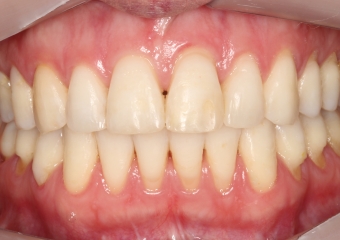

Oclusão após a cirurgia